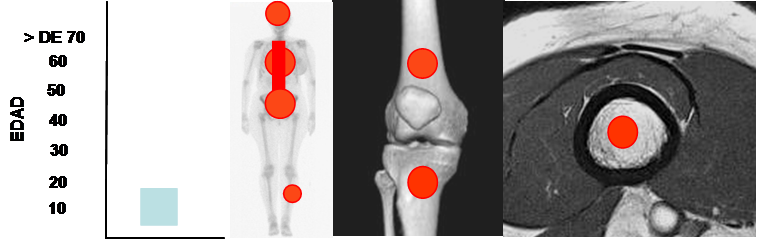

Fig 128. Granuloma eosinófilo.

Mayor frecuencia entre los 5 y 15 años. Predominio en los huesos planos, columna y huesos largos. Lesión metafisodiafisiaria, de ubicación central.